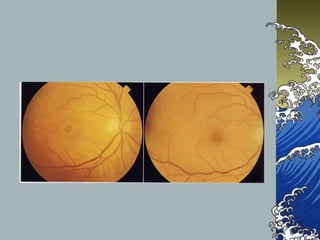

Stage 4

- FTMH with complete PVD

- may be associated to ERM

- FFA in stage 3 , 4 - mottle

hyperfluorescene from RPE thining, RPE

depigment, loss of xanthophyl

MH stage IV